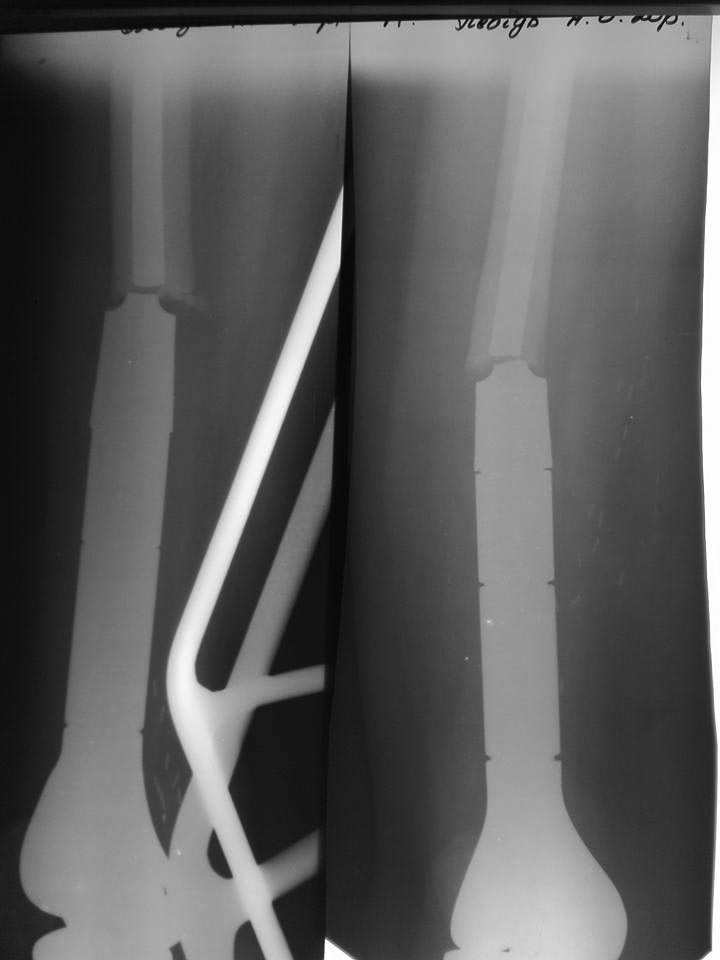

Перелом онкологического эндопротеза

2010. Stryker. Саркома. Девочка 20 лет.

Какие решения есть?

Выбить сломанную часть из бедра через вертел, реэндопротезирование!